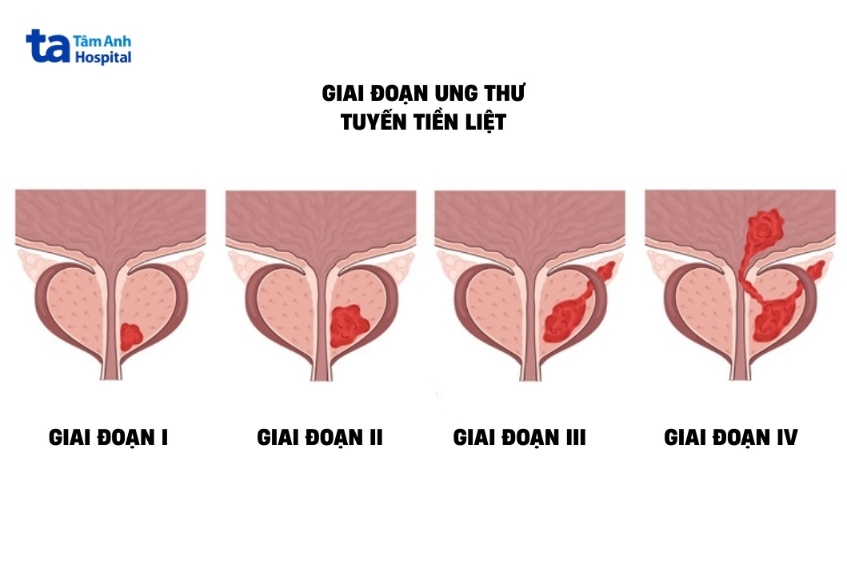

Ung thư tuyến tiền liệt giai đoạn 3 (hay III) là giai đoạn khối u đã phát triển lớn ra ngoài lớp bao của tuyến tiền liệt, có thể lan tới túi tinh (giai đoạn 3B) hoặc không (3A). Tuy nhiên, ở giai đoạn 3, ung thư chưa lây lan đến hạch bạch huyết lân cận cũng như các cơ quan khác.

Mỗi yếu tố sẽ được chia thành nhiều giai đoạn cụ thể, ví dụ T0 (không có khối u), T1 (u không rõ ràng, không sờ thấy), N0 (không có di căn hạch vùng), M0 (không có di căn)… Với ung thư tuyến tiền liệt giai đoạn 3, người bệnh không có di căn hạch vùng (N0) và di căn xa (M0).

Ung thư tuyến tiền liệt giai đoạn 3A được biểu diễn dưới dạng T1-2N0M0, PSA≥20 và độ mô bệnh học từ 1-4. Có thể diễn giải như sau: khối u có thể không rõ ràng (T1) hoặc đã phát triển rõ nhưng chưa xâm lấn đến lớp bao tuyến tiền liệt (T2), không có di căn hạch vùng (N0) hay di căn xa (M0) và điểm PSA phải tối thiểu 20, độ mô bệnh học từ 1-8 điểm.

Người bệnh ung thư tuyến tiền liệt được xác định giai đoạn 3B trong trường hợp T3-4N0M0, chỉ số PSA bất kỳ, độ mô học từ 1-4. Tức người bệnh có khối u nguyên phát đã ra khỏi bao tuyến tiền liệt (T3) nhưng chưa xâm lấn qua các cơ quan khác hoặc xâm lấn các cơ quan lân cận (T4) như túi tinh, bàng quang, cơ vòng hậu môn, trực tràng… Chưa có di căn hạch vùng (N0) và di căn xa (M0). Độ mô bệnh học từ 1-8 điểm, nồng độ PSA ở mọi mức bất kỳ.

Giai đoạn 3C được xác định thông qua độ mô bệnh 9-10 điểm (độ 5) với tình trạng khối u bất kỳ (T1-4) và PSA ở mọi mức độ, không di căn hạch vùng (N0) hay di căn xa (M0).

Có thể bạn quan tâm: Đặc điểm 4 giai đoạn ung thư tuyến tiền liệt.